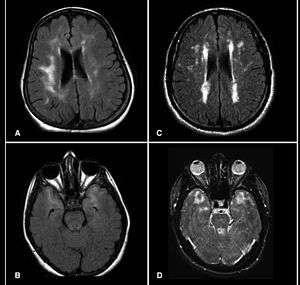

| Brain MRI from patients with CADASIL showing multiple lesions. | |

MRIs show hypointensities on T1-weighted images and hyperintensities on T2-weighted images, usually multiple confluent white matter lesions of various sizes, are characteristic. These lesions are concentrated around the basal ganglia, peri-ventricular white matter, and the pons, and are similar to those seen in Binswanger disease.[2][7] These white matter lesions are also seen in asymptomatic individuals with the mutated gene.[8] While MRI is not used to diagnose CADASIL, it can show the progression of white matter changes even decades before onset of symptoms.